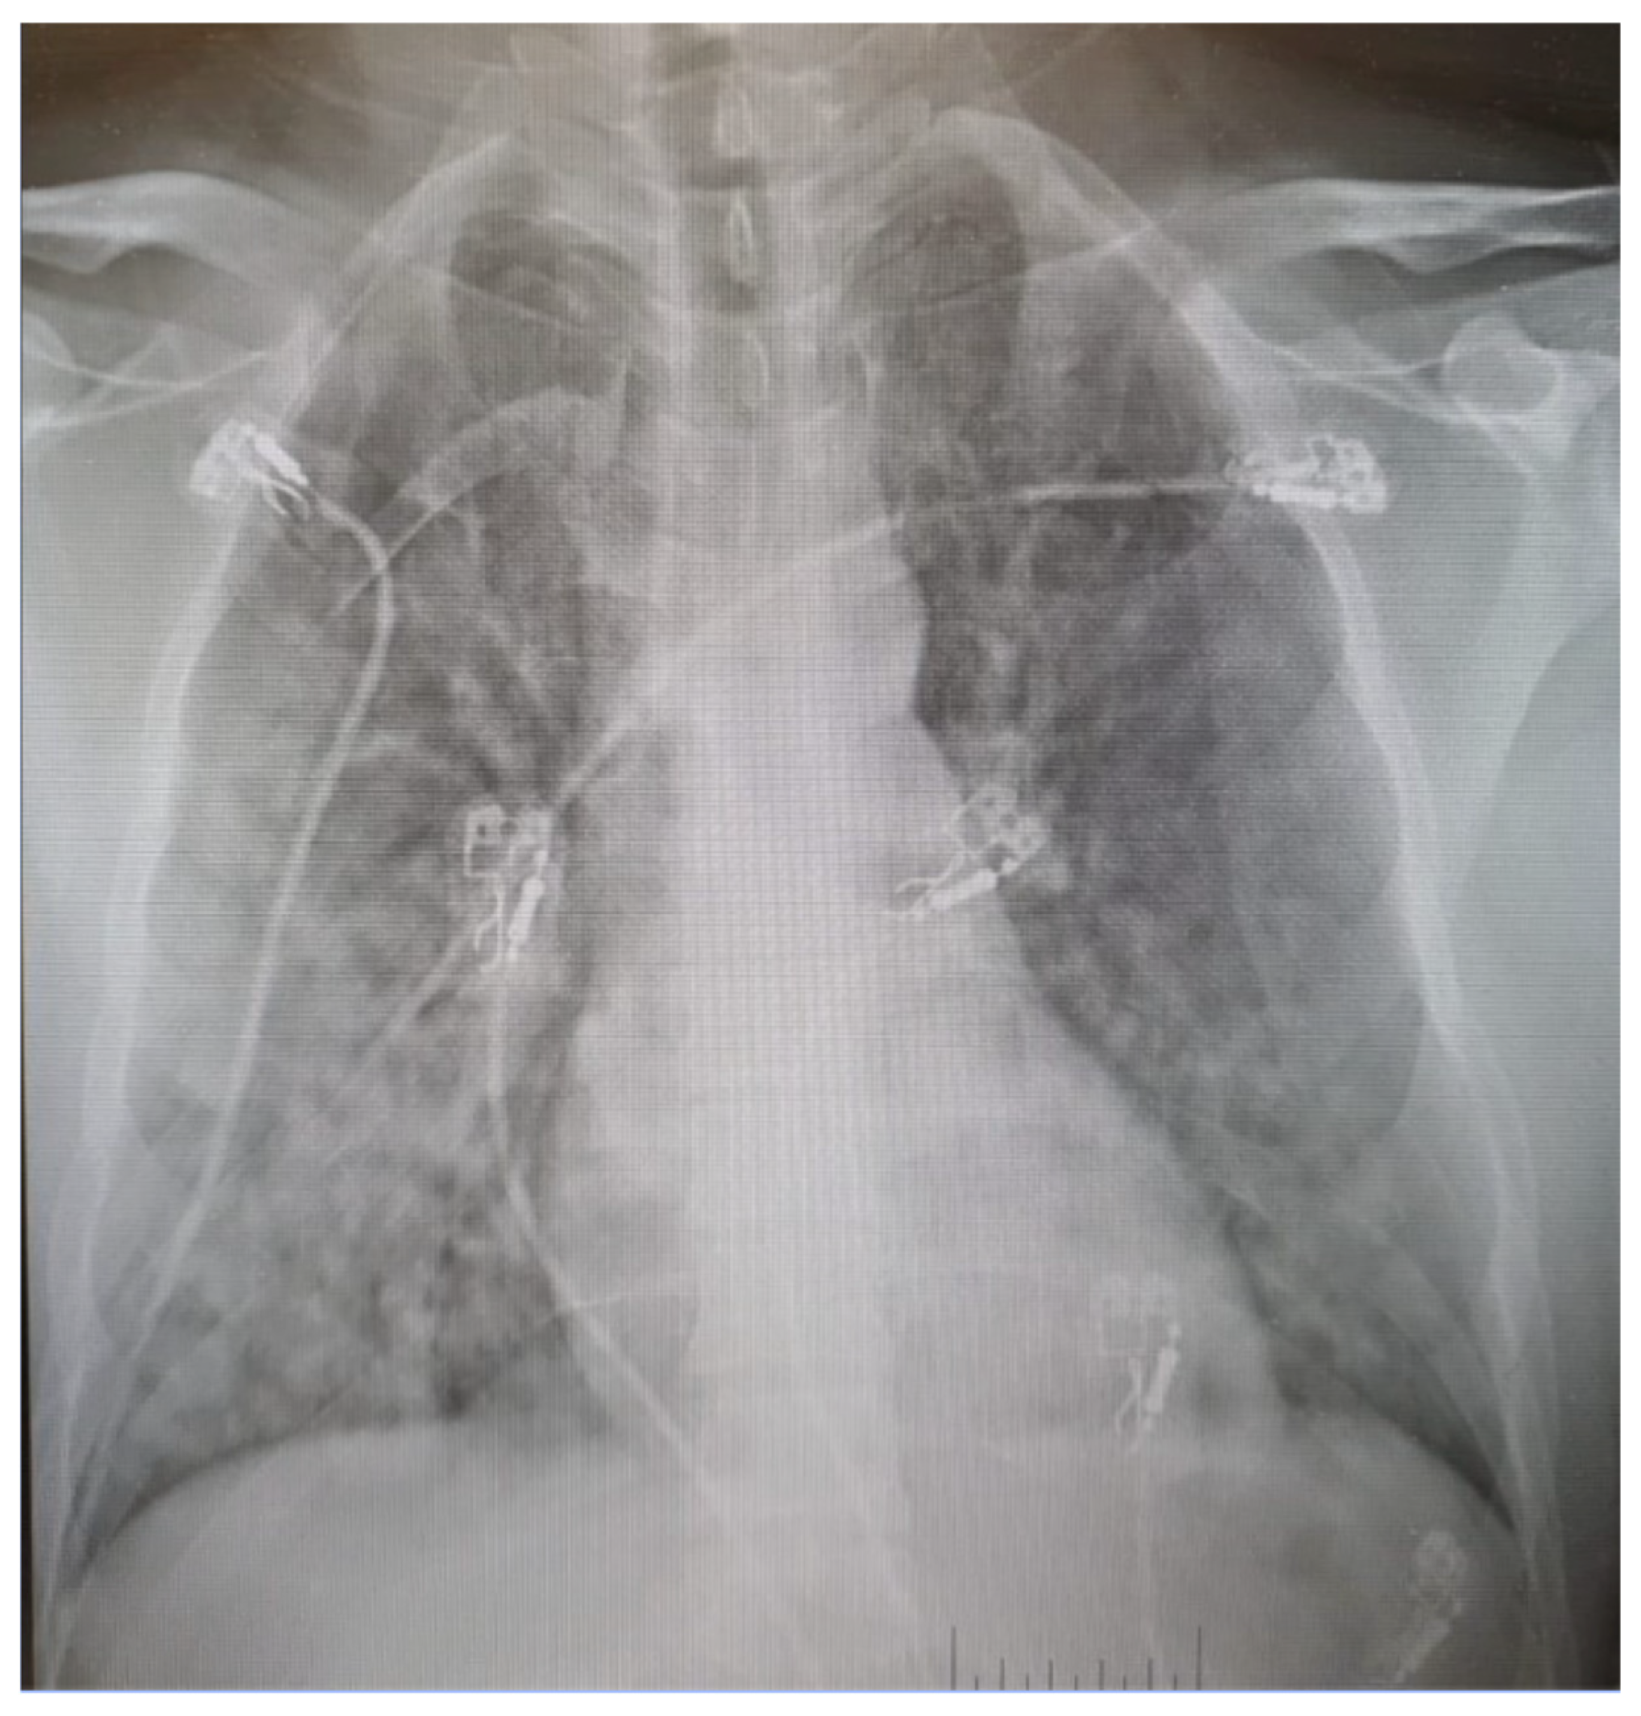

2. Case Presentation

- Nowadly, C.D.; Solomon, A.J.; Burke, S.M.; Rose, J.S. Evaluation of Serial Chest Radiographs of High-Altitude Pulmonary Edema Requiring Medical Evacuation from South Pole Station, Antarctica: From Diagnosis to Recovery. Mil. Med. 2021, 186, e1135–e1139. [Google Scholar] [CrossRef] [PubMed]